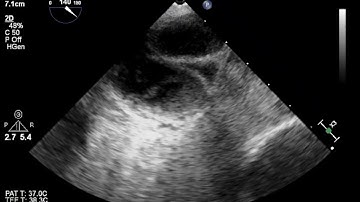

Detection of Left Atrial Appendage Thrombus by TEE